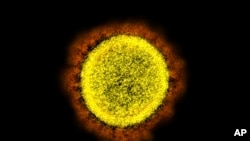

XBB.1.5是目前最具传播性的新冠病毒变种,是XBB的一个分支,是于去年10月首次被发现的。

这个目前已占主导地位的XBB相关亚变种源自奥密克戎的BA.2版本。